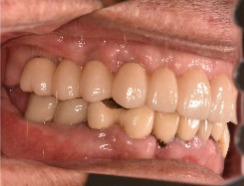

女性Hさん 60代(オールセラミック冠・インプラント)

主訴

右下のブリッジがゆらゆら動く。

治療内容

ブリッジの支台になっている奥の歯が、被せ物の中で虫歯になり、支台の役割を果たさず、前方の歯のみで支えられていました。前方の歯をそのままにして、後方の部分を切り離すと、そのまま取れてきました。中は、虫歯で歯根しか残っていない状況でした。この歯は、根管治療後、単独でオールセラミック冠を被せ、歯のないところにインプラントを埋入しました。

所感

今回の治療法には、次の3つの方法があります。

(1)虫歯になっていた歯の根管治療をし、土台を入れ、また再びブリッジにする。しかし、虫歯になっていたほうの歯は、ブリッジの支台として使うには、心もとなく長持ちしない可能性が高く、今度問題が生じたときには抜歯になる。

(2)虫歯になっていた歯に、単独で被せ物をし、歯のないところに1本だけの部分入れ歯を入れる。取り外しの入れ歯なので、自分の歯のような感覚で噛むことはできない。この方法も歯のない部分の負担を欠損の両側の歯に負担してもらうため、長持ちしない可能性が高い。

(3)虫歯になっていた歯に、単独で被せ物をし、歯のないところにインプラントを埋入する。欠損している部分の負担を前後の歯に負担させないので、歯を守ることができる。また、自分の歯と同じ感覚で食事をすることができる。

患者さんは、3つ目の方法を選択されました。一番長持ちし、これ以上歯を失わないためには、最良の方法だと考えます。

オールセラミック冠(失活歯):¥104,500(税込)

インプラント:¥363,000(税込)

合計:¥467,500(税込)

Before

冠の中で大きな虫歯になり支台の役割を果たしていませんでした。

【インプラント埋入前】

冠はブリッジを切断しただけで取れてきました。軟化象牙質を取り除いたところ、歯根しか残っていない状況で保存できるかどうかのぎりぎりのところでした。

After